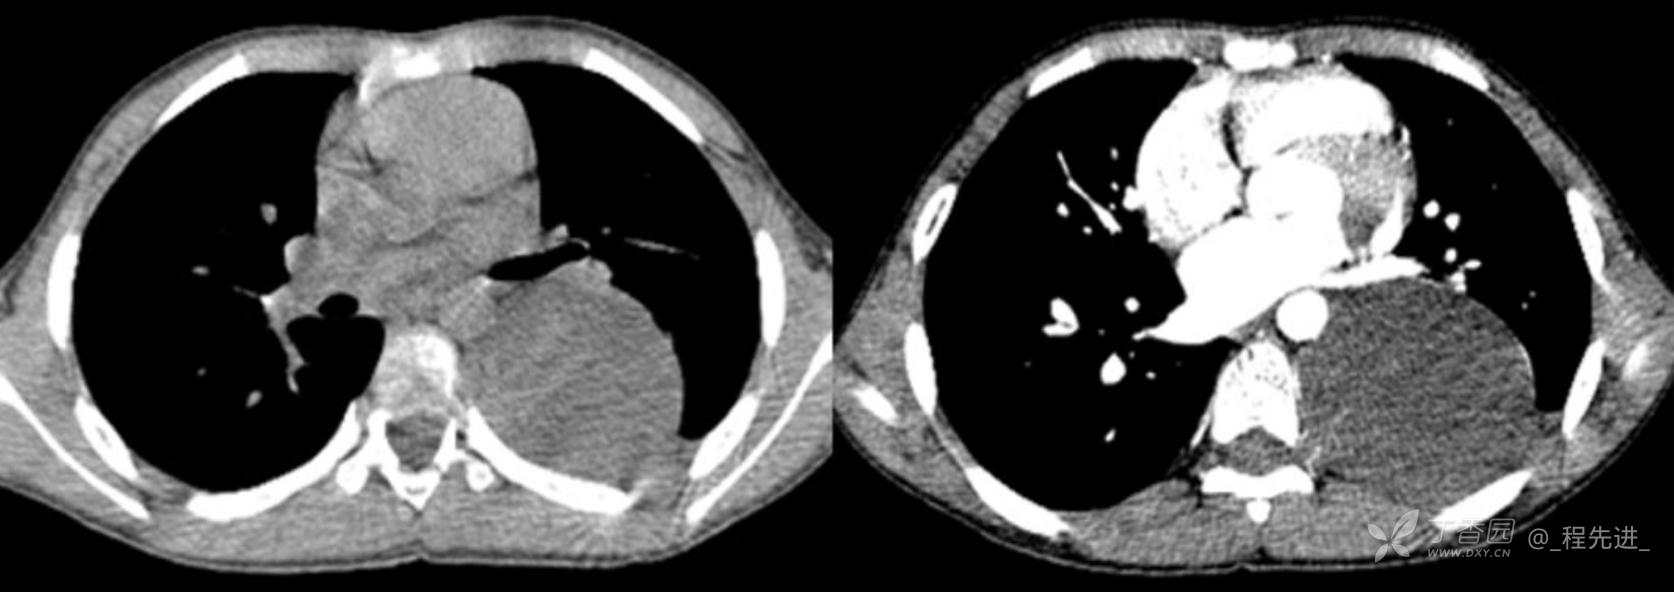

11月特别精彩病例|胸片示“左侧胸腔包裹性积液”,CT增强你诊断啥?【病理已公布】

呱呱叫了 等 3 位达人已点赞男,11岁,患儿因其爷爷近期在我院诊断“肺结核”,于外院行结核筛查,胸片示“左侧胸腔包裹性积液”,近期无咳嗽、发热、纳差、盗汗、乏力、胸痛、胸闷、气促不适,精神反应可,为求明确“左侧胸腔包裹性积液”病因,遂来我院门诊就诊,门诊以“胸腔积液查因”收住入院。发病以来,精神尚可食欲如常,大便如常,小便量如常,体重无明显变化